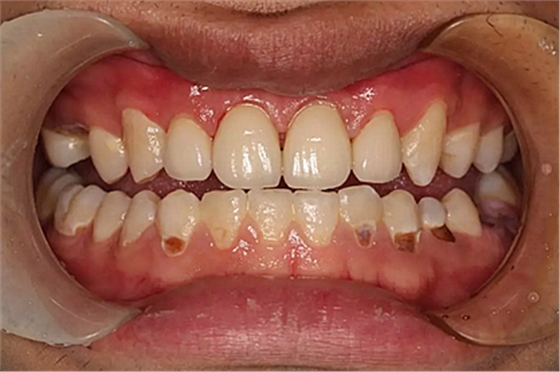

現(xiàn)在剩下的任務(wù)就是為我其他的兄弟姐妹們治療了。需要做根管的做根管,需要做冠的做冠,需要樹脂充填的做樹脂充填。前前后后主人帶我們進(jìn)行了12次的復(fù)診,歷時(shí)6個(gè)月,現(xiàn)在的我們是這樣的

再來看看曾經(jīng)的我們